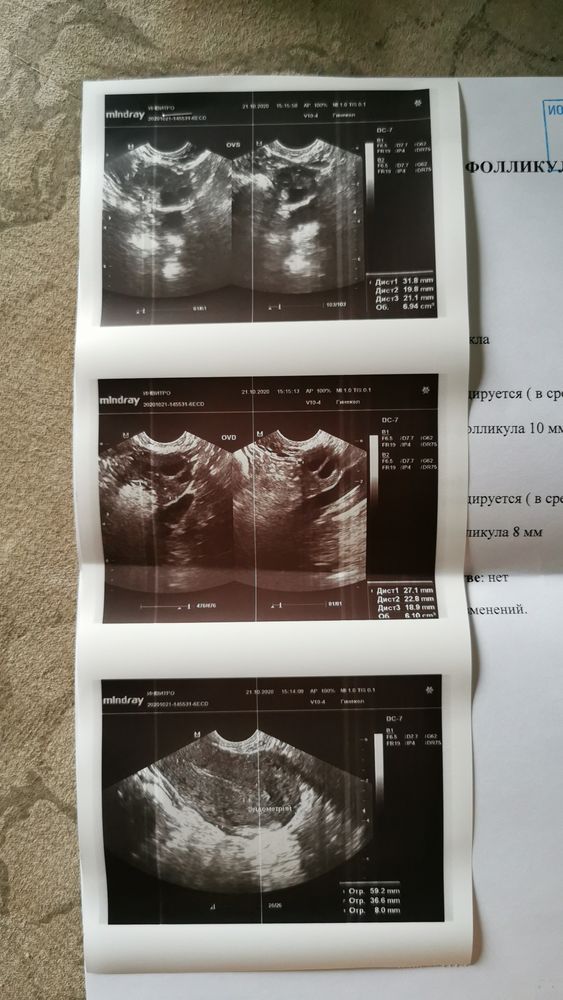

УЗИ фолликулометрии

У меня овуляция вообще на 19-22дц. А в прошлом цикле делала фолликулометрию, тоже написали фолликулы до 4-6мм и врач сказал, что 100% не будет овуляции. В итоге овуляция была и хорошая. Правда не знаю на какой день цикла. цикл 31-34дня.

А у вас вообще фолликул 10мм максимальный, так что будет 100%

У меня на 14 дц был фолликул 13 мм, думала дорастёт, но узист сказал, что цикл будет ановуляторный. В итоге овуляции и правда тогда не было. Поэтому тут 50/50, только следить за ростом фоллика каждые 2 дня

У меня в этом цикле был фолик такой же как у вас, и в такой же день цикло. Овуляция была на 19 день цикла